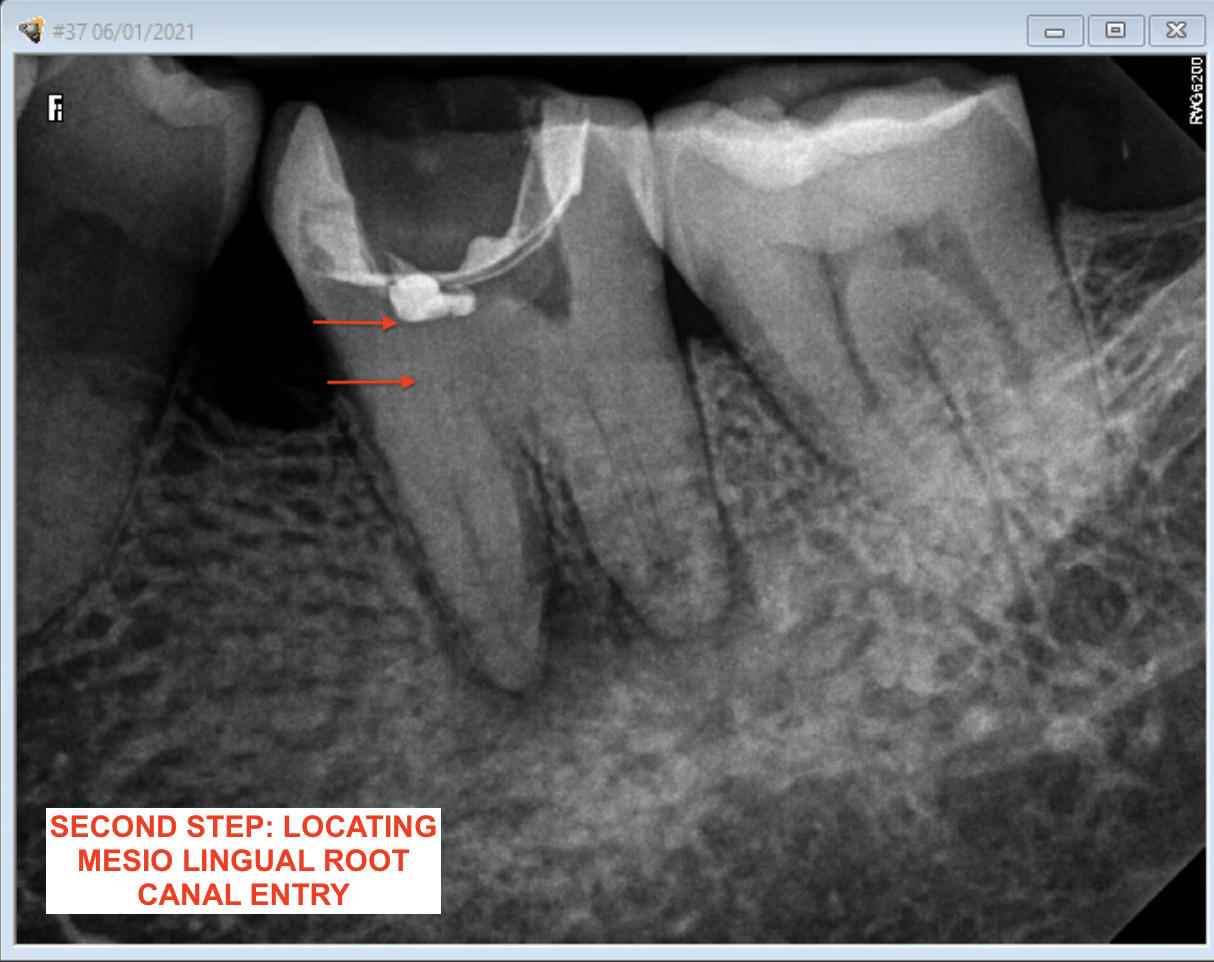

What Is A Calcified Root Canal. a canal in a tooth is classed as calcified when the canal space shrinks. what are calcified root canals? what is a calcified tooth? This condition is better known as. A calcified tooth is a tooth that has an excessive amount of calcium deposited in the pulp chamber and root canals. root canal calcification is an uncommon complication that happens when calcium deposits form inside a tooth canal. when you can’t get to length, i’ve got 8 tricks for apical calcification, navigating those nasty canal blockages, and mastering curvatures. Successful root canal treatment depends on the. This procedure can be difficult to complete, because the. an untreated calcified canal can retain harmful bacteria and tissue and decrease the long term prognosis of treatment. Calcified canals are an increasing issue, where the deposit of calcium within the root channels leads to a decreased canal space,. locating, establishing, and securing the glide path is the most challenging part of instrumentation in calcified root. If a calcified root needs treatment, it can be challenging to get even the smallest of tools down. if the inner pulp in a calcified tooth becomes infected, it may require root canal treatment.

Successful root canal treatment depends on the. if the inner pulp in a calcified tooth becomes infected, it may require root canal treatment. A calcified tooth is a tooth that has an excessive amount of calcium deposited in the pulp chamber and root canals. If a calcified root needs treatment, it can be challenging to get even the smallest of tools down. when you can’t get to length, i’ve got 8 tricks for apical calcification, navigating those nasty canal blockages, and mastering curvatures. This procedure can be difficult to complete, because the. Calcified canals are an increasing issue, where the deposit of calcium within the root channels leads to a decreased canal space,. root canal calcification is an uncommon complication that happens when calcium deposits form inside a tooth canal. what are calcified root canals? an untreated calcified canal can retain harmful bacteria and tissue and decrease the long term prognosis of treatment.

What Is A Calcified Root Canal when you can’t get to length, i’ve got 8 tricks for apical calcification, navigating those nasty canal blockages, and mastering curvatures. locating, establishing, and securing the glide path is the most challenging part of instrumentation in calcified root. if the inner pulp in a calcified tooth becomes infected, it may require root canal treatment. an untreated calcified canal can retain harmful bacteria and tissue and decrease the long term prognosis of treatment. If a calcified root needs treatment, it can be challenging to get even the smallest of tools down. what is a calcified tooth? Successful root canal treatment depends on the. a canal in a tooth is classed as calcified when the canal space shrinks. This procedure can be difficult to complete, because the. This condition is better known as. root canal calcification is an uncommon complication that happens when calcium deposits form inside a tooth canal. Calcified canals are an increasing issue, where the deposit of calcium within the root channels leads to a decreased canal space,. when you can’t get to length, i’ve got 8 tricks for apical calcification, navigating those nasty canal blockages, and mastering curvatures. what are calcified root canals? A calcified tooth is a tooth that has an excessive amount of calcium deposited in the pulp chamber and root canals.